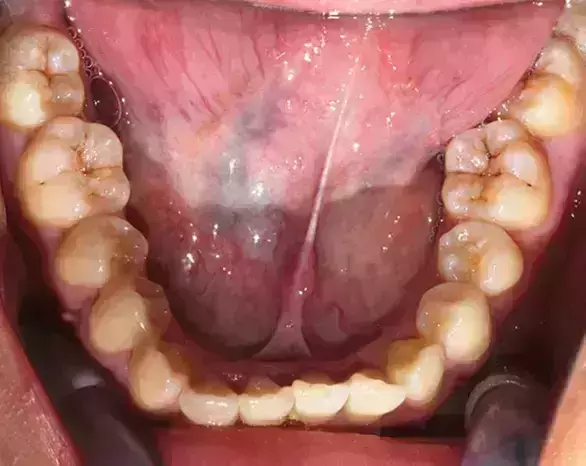

Damon 病例分享:安氏 II 類(lèi)二分類(lèi)露齦笑的矯治(董一磊)

治療前后對(duì)比